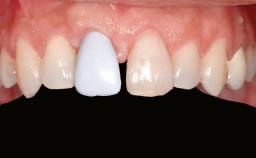

An 18-year-old man was referred for implant therapy in the posterior mandible to the Department of Oral Surgery and Stomatology (University of Bern, Switzerland). He was healthy and did not smoke. Tooth 35 was congenitally missing, involving a single-tooth edentulous space that offered an adequate mesiodistal dimension for implant placement but exhibited a typical pattern of buccal flattening. A panoramic radiograph was obtained, which revealed a sufficient vertical bone height above the mandibular canal and a normal bone structure in the edentulous area.